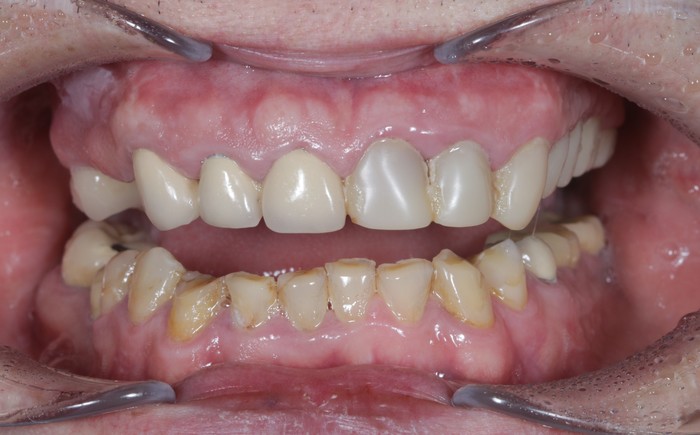

Вот пример того, когда пациент пренебрёг данным правилом:

Мужчине были установлены и спротезированы (временными коронками) имплантаты в другой клинике. После этого он пропал на несколько лет, не закончив полностью свое лечение. Явился лишь тогда, когда почувствовал «дискомфорт».

Кроме несостоятельности старых коронок и пломб, патологической стираемости зубов и т.д. - все эти годы сильно страдала гигиена.